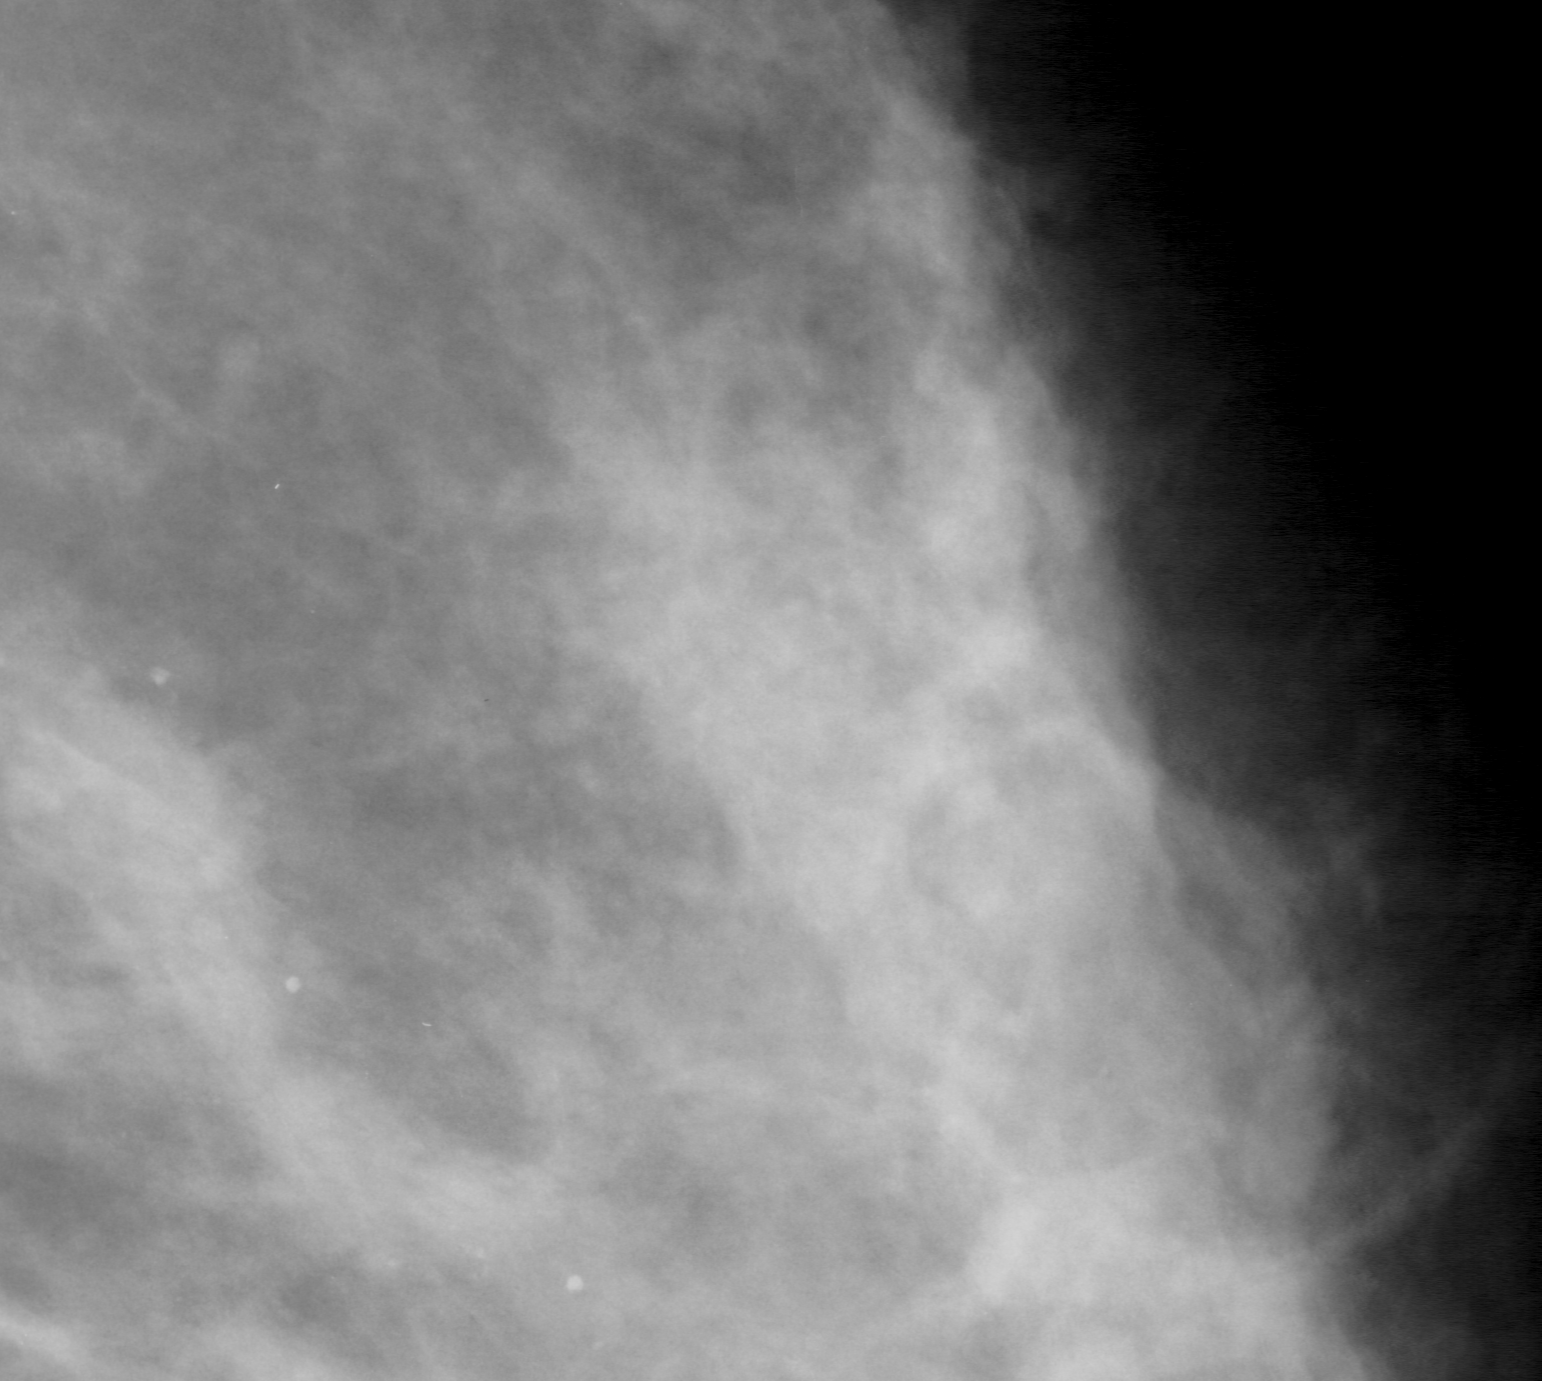

In our experiments, we use the Digital Database for Screening Mammography (DDSM) [4], a collaboratively maintained public dataset at the University of South Florida. It comprises approximately 2500 studies each containing both mediolateral oblique (MLO) and craniocaudal (CC) views of each breast. Each image is grayscale and accompanied by a mask specifying the region of the pre-segmented mass if present. Examples of benign and malignant masses are shown in Fig. 1.